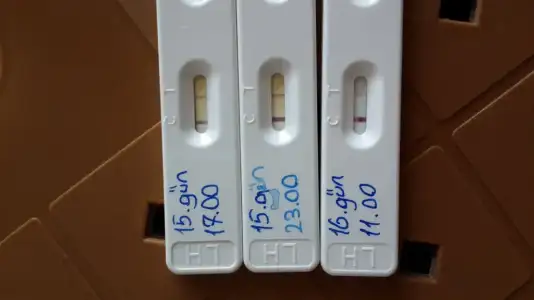

Aynen canim ya :)) hehehe nub fotosuda aticam yarin fikir olsunsibel canım çok sevindim RABBİM tamamına erdirsin hayırlısı ile sağ salim kucağımıza alalım inşallah. darısı diğer arkadaşlarında başına inşallah. seninde dediğin gibi bebeğin önce sağda kese sonra tavana yapışmış